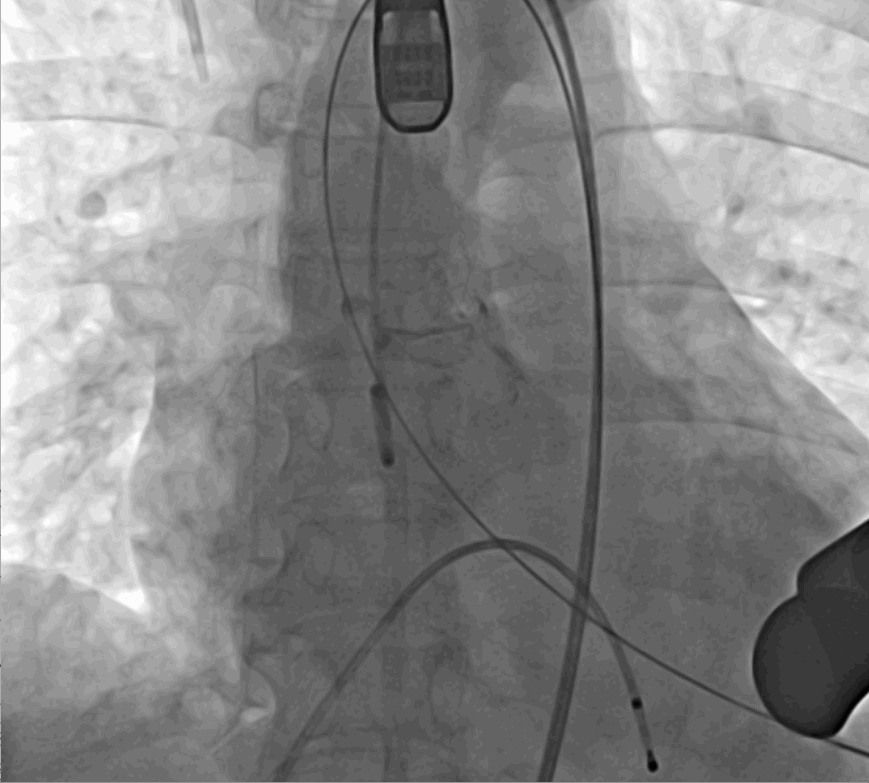

術(shù)中釋放定位鍵后DSA影像圖

手術(shù)采用經(jīng)心尖入路,對(duì)患者進(jìn)行全麻后,在左側(cè)心尖處做3-4cm微創(chuàng)手術(shù)切口,在DSA及超聲引導(dǎo)下手術(shù)順利完成。從導(dǎo)入器械到完成瓣膜置入,僅耗時(shí)約10分鐘。術(shù)后即刻主動(dòng)脈瓣返流程度由術(shù)前大量返流轉(zhuǎn)為消失,患者于導(dǎo)管室拔除氣管插管,次日由ICU轉(zhuǎn)入普通病房。